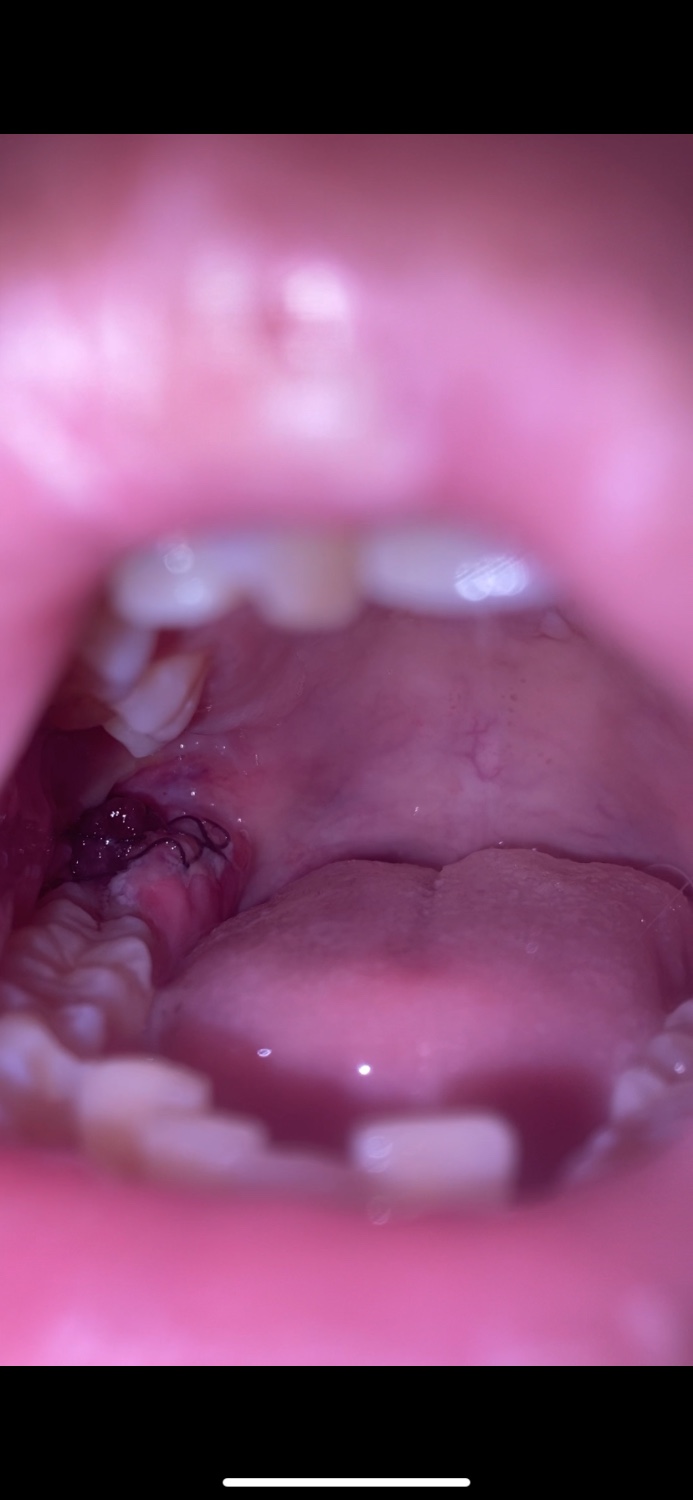

แผลฟันคุดมีก้อนๆน้ำตาลอย่างงี้ปกติมั้ย

ตอนแรกมันก็ไม่มีขึ้นมาแต่พอผ่านอีกวันมันก็ขึ้นมามันติดเชื้อหรืออะไรมั้ยครับกังวลมากม ตามรูปเลยครับ